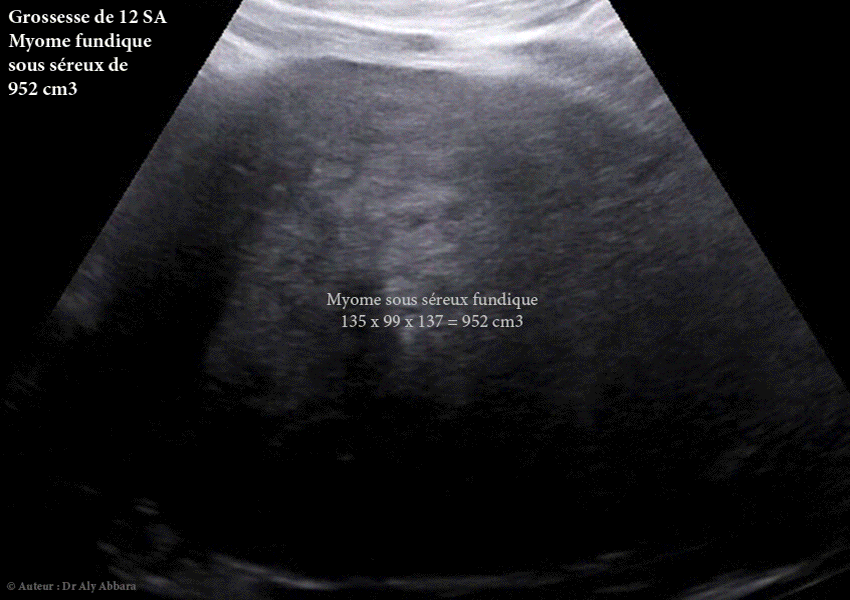

Il s'agissait d'un myome découvert fortuitement lors de la première échographie de datation (à 10 SA puis à 12 SA), chez une jeune femme, primipare de 31 ans. Une dégénérescence nécrotique kystique du myome est survenue dès le milieu du deuxième trimestre de la grossesse. L'enkystation nécrotique est devenue quasi totale au début de la 6ème mois de grossesse.

Ce phénomène de dégénérescence kystique était associé à une augmentation volumique rapide du myome jusqu'au milieu du 6ème de grossesse : 952 cm3 à 12 SA ; 979 cm3 à 17 SA ; 1902 cm3 à 23 SA, puis 2446 cm3 à 25 SA.

À 12 SA (952 cm3).